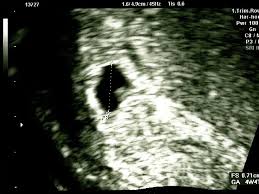

Pada pemeriksaan USG janin 2 minggu, dokter mungkin belum bisa melihat janin secara langsung, tetapi tanda pertama yang biasanya terlihat adalah kantung kehamilan. Kantung ini adalah struktur berisi cairan yang mengelilingi embrio yang sedang berkembang. Kehadirannya menjadi salah satu indikasi awal yang paling jelas bahwa Anda benar-benar hamil. Melihat kantung ini saja sudah bisa membuat Anda merasa tenang dan bahagia, karena ini adalah rumah pertama bagi si kecil.

Berbarengan dengan kantung kehamilan, ada kemungkinan terlihat juga yolk sac atau kantung kuning telur. Jangan salah paham, ini bukan kuning telur seperti pada ayam, ya. Yolk sac adalah struktur kecil berbentuk lingkaran yang berfungsi sebagai sumber nutrisi utama bagi embrio selama beberapa minggu pertama, sebelum plasenta terbentuk sepenuhnya. Kehadiran yolk sac ini merupakan tanda penting bahwa kehamilan berjalan dengan baik.